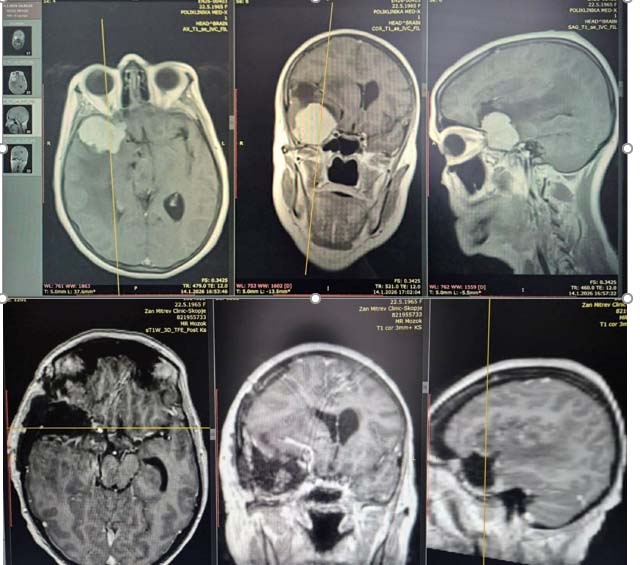

Пациентката беше примена со прогресивна психомоторна забавеност, проблеми со меморијата и памтењето во изминатите 4 месеци, а во неколку наврати и проблем со рамнотежата и пад. По направените радиолошки иследувања со нуклерна магнетна резонанца, кај пациентката беше дијагностициран туморски процес во мозокот, по што следуваше индикација за оперативно лекување.

Сликата во прилог пред и постоперативно: